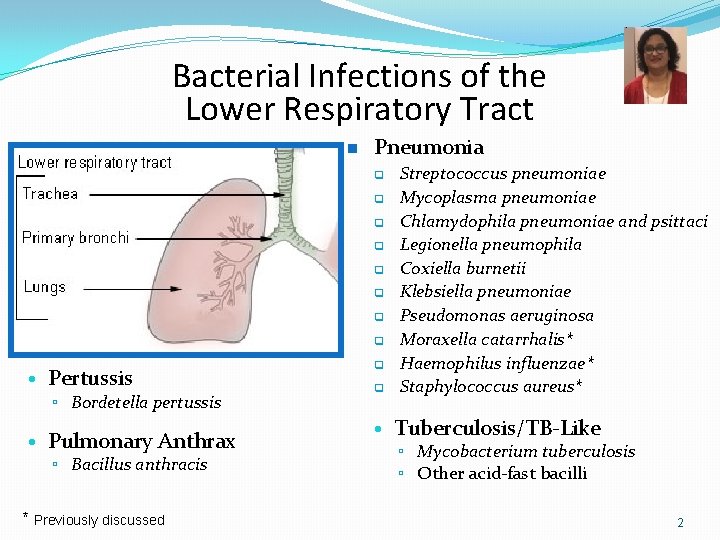

Bacterial Infections of the Lower Respiratory Tract n Pneumonia q q q q • Pertussis ▫ Bordetella pertussis • Pulmonary Anthrax ▫ Bacillus anthracis * Previously discussed q q Streptococcus pneumoniae Mycoplasma pneumoniae Chlamydophila pneumoniae and psittaci Legionella pneumophila Coxiella burnetii Klebsiella pneumoniae Pseudomonas aeruginosa Moraxella catarrhalis* Haemophilus influenzae* Staphylococcus aureus* • Tuberculosis/TB-Like ▫ Mycobacterium tuberculosis ▫ Other acid-fast bacilli 2

Types of Pneumonia Clinical findings Onset Acute Chronic Typical pneumonia Atypical pneumonia Setting Community acquired Nosocomial

Based on the setting in which the infection was acquired… Pneumonia NOSOCOMIAL COMMUNITY ACQUIRED ASPIRATION PNEUMONIA